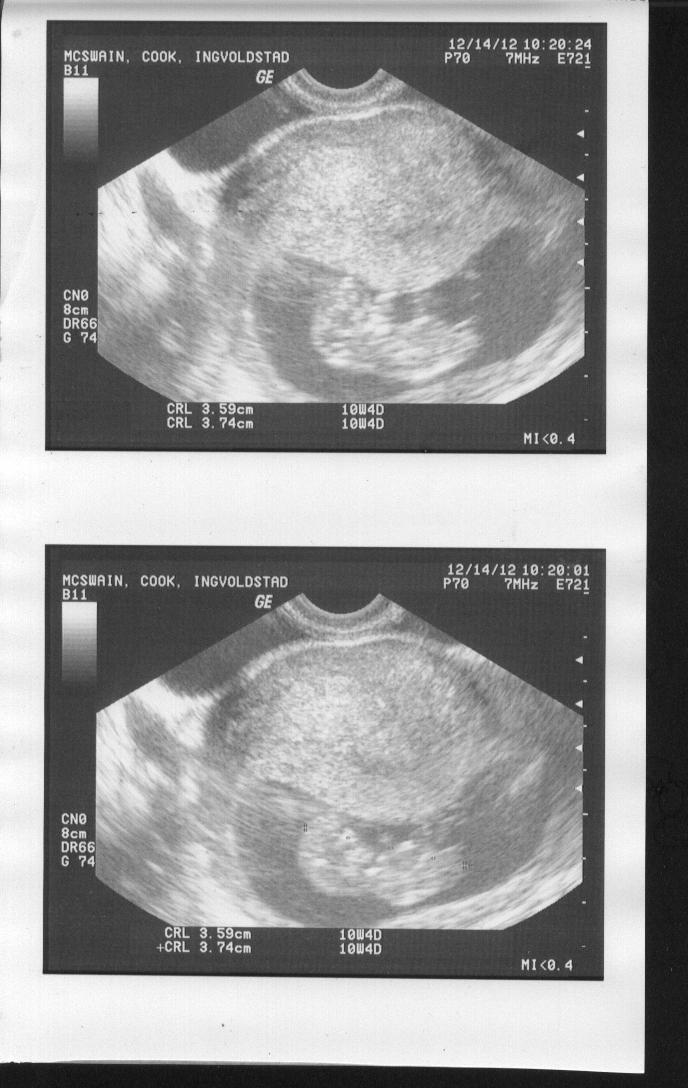

Hey there! I know it's super early, but would love to hear your guesses. I am so excited to find out what this baby is!

Attachment 7251